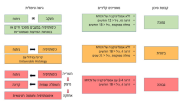

| 07:42, 12 באוגוסט 2023 | רטינובלסטומה 2.png (קובץ) |  |

79 קילו־בייטים | Motyk | 1 | |

| 18:29, 11 באוגוסט 2023 | רטינובלסטומה1.png (קובץ) |  |

83 קילו־בייטים | Motyk | 1 | |

| 05:34, 11 באוגוסט 2023 | INRG 2.png (קובץ) |  |

216 קילו־בייטים | Motyk | 1 |